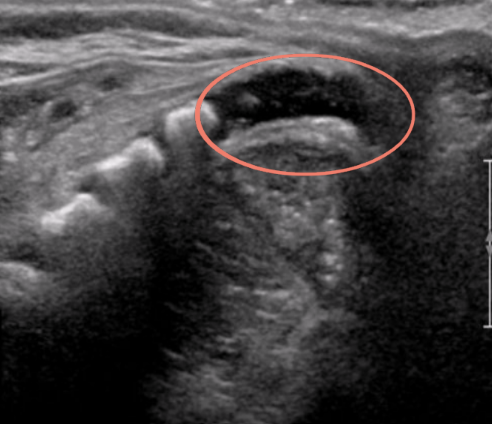

circle

coccyx

1

spinal cord

2

conus medullaris

3

central echo complex in hypoechoic spinal cord

4

filum terminale and nerve roots

5

unossified coccyx

arrow

lumbosacral joint

is this spine normal?

yes